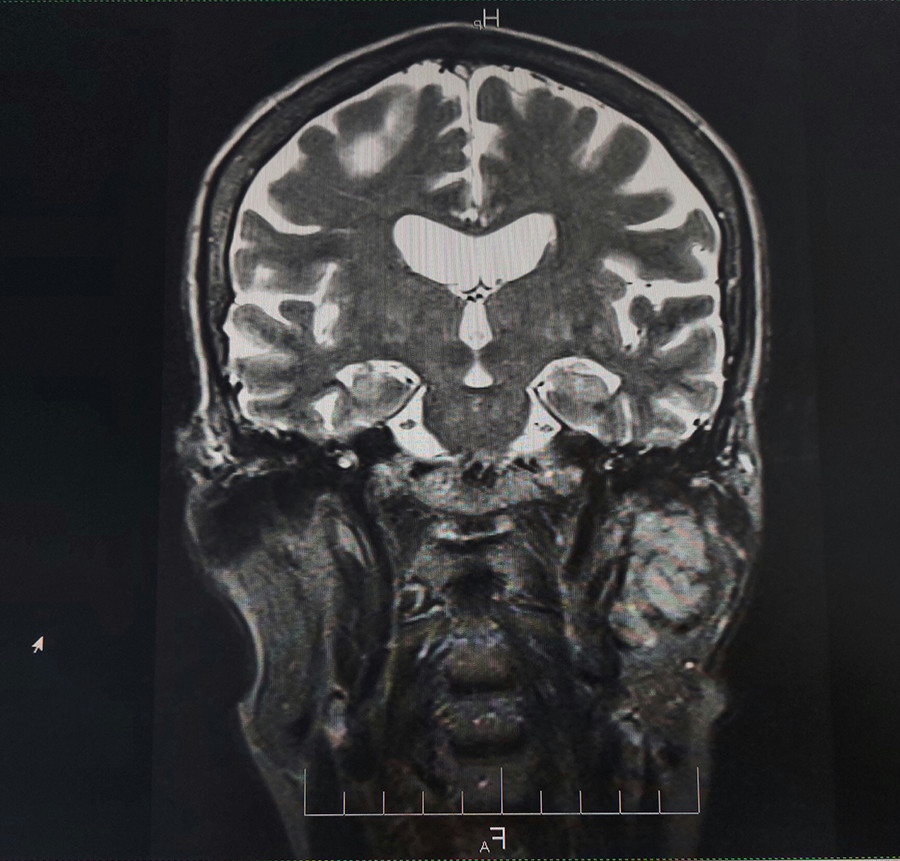

Նախքան «Նաիրի» ԲԿ դիմելը պացիենտի մոտ ախտորոշվել է հարականջային թքագեղձի ադենոմա։ «Նաիրի» բժշկական կենտրոնում կատարվել է թքագեղձի մագնիսա-ռեզոնանսային տոմոգրաֆիա, և պարզվել, որ ավելի քան 5 տարի գոյություն ունեցող թքագեղձի ադենոմայի ներսում առկա է մոտավորապես 1 սմ պինդ գոյացություն։ Իրականացվել է հայտնաբերված պինդ գոյացության պունկցիոն բիոպսիա և, արդյունքում, ախտորոշվել է ուռուցք` թքագեղձի ադենոկարցինոմա: Սա այն դասական դեպքերից է, թե ինչպես կարող է բարորակ գոյացությունը, տարիներ շարունակ անտեսելու, չբուժելու արդյունքում վերաճել չարորակ ուռուցքի։